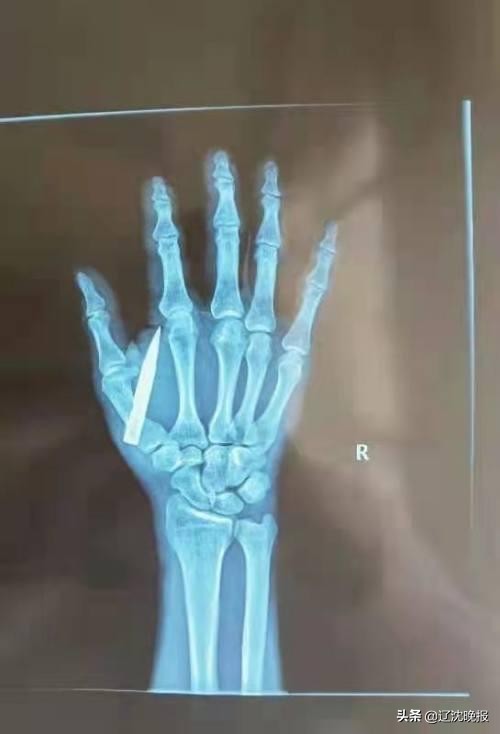

据北部战区总医院烧伤整形科刘双阳主任医师介绍,石先生刚到医院时,手掌被鱼镖贯穿。鱼镖整个处于虎口区,从手背露出一个两三毫米的针尖。金属镖完全镶在肌肉组织里。拍片子可见第一掌骨肌底骨折,第一背侧骨间肌完全断裂。幸运的是动脉和神经躲过了鱼镖的破坏。

“手术中除了取出镖体外,还对骨折部位进行了复位。伤口没有发生明显感染。目前还在恢复当中。恢复良好的话,不会影响正常生活。”刘医院生说,“术中探查发现,镖体距离动脉仅0.5厘米。如何伤到动脉,可能引发大出血,危机生命。伤到神经和肌腱的话,也可能会影响以后手指的屈伸功能。”